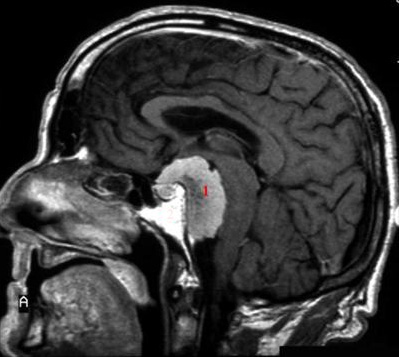

Meningeom, MR med kontrast

MR skanning med kontrast - sagittalt snit.

1. Meningeomet ses tydeligere da det optager kontrastmiddel.

Det ligger så det kan påvirke synsnerven og hypofysen, samt påvirke hjernestammen.